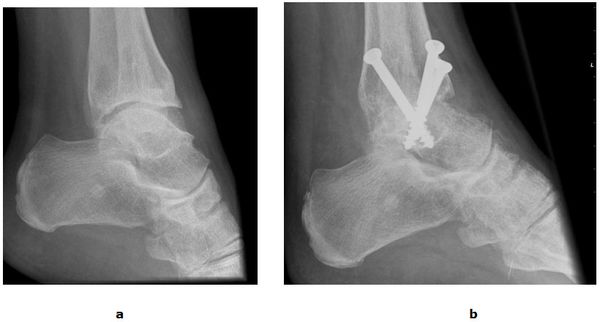

Abb.1: a Oberes Sprunggelenk von vorne. b und von der Außenseite.

Die fortgeschrittene Arthrose des oberen Sprunggelenkes kann sehr schmerzhaft sein und die normale Fortbewegung stark beeinträchtigen. Die Versteifung des Gelenkes (Arthrodese) war Jahrzehnte lang die Therapiemethode der Wahl. Trotz einer Verbesserung der Schmerzsituation berichten Patienten über Probleme bei der Mobilisation. Hierunter fallen Schwierigkeiten beim Treppen steigen und beim aufstehen vom Stuhl. Im Laufe der Zeit können Schmerzen in überlasteten Nachbargelenken auftreten (Anschlussarthrosen) und das ohnehin hölzerne Gangbild weiter verschlechtern. Weitere Nachteile liegen in dem hohen Infektionsrisiko, der langen Rekonvaleszenzzeit (3 Monate Gips) und dem hohen Risiko einer Falschgelenkbildung (Pseudarthrose).

Abb.5: a Arthrose mit kontrakter Spitzfußstellung des oberen Sprunggelenkes. b Korrigierende Fusion mit drei Schrauben.

Die rekonstruktive Versorgung mit einer Sprunggelenksendoprothese ermöglicht dem Patienten im Vergleich zur Fusion eine wesentlich schnellere Mobilisierung mit Erhalt der Abrollvorgänge. 6 Wochen nach dem operativen Eingriff ist in der Regel das Laufen ohne Gips mit voller Belastung erlaubt. Dennoch eignet sich nicht jedes Gelenk für eine Endoprothese. In Fällen von hochgradigen Bandinstabilitäten oder erheblichen Knochenverformungen ist weiterhin die Fusion die Therapie der Wahl.